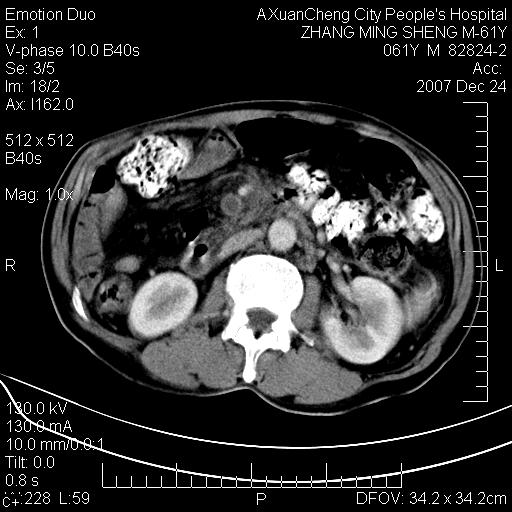

标题: CT11031:M61Y,胰腺占位 [打印本页]

标题: CT11031:M61Y,胰腺占位

大家侃侃门静脉和胆管系统怎么回事,肝内转移?

胰腺癌肝转移

肝硬化,门脉高压,脾肿大;弥漫性肝癌,肝内、门脉、腹膜后淋巴结转移,肝内外胆管扩张,胰头区占位,建议mr检查

胰腺癌伴肝内转移;门脉、肠系膜上v癌栓形成。

考虑为:胰腺癌伴肝脏转移、腹膜后淋巴结转移,门静脉及肠系膜上静脉瘤栓形成。

胰体尾癌伴肝内转移,门静脉及肠系膜上静脉瘤栓形成.

肝硬化,脾大. 胰腺癌伴肝内转移;门脉、肠系膜上v癌栓形成。